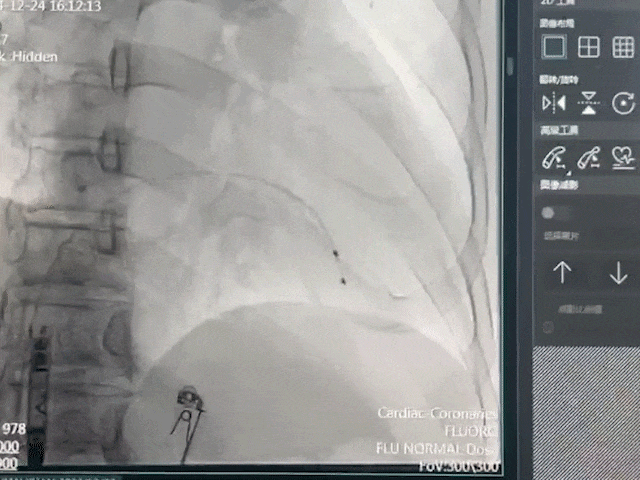

手术过程部分展示

调弯跨三尖瓣进入右室低位间隔

右前30°造影,位置理想